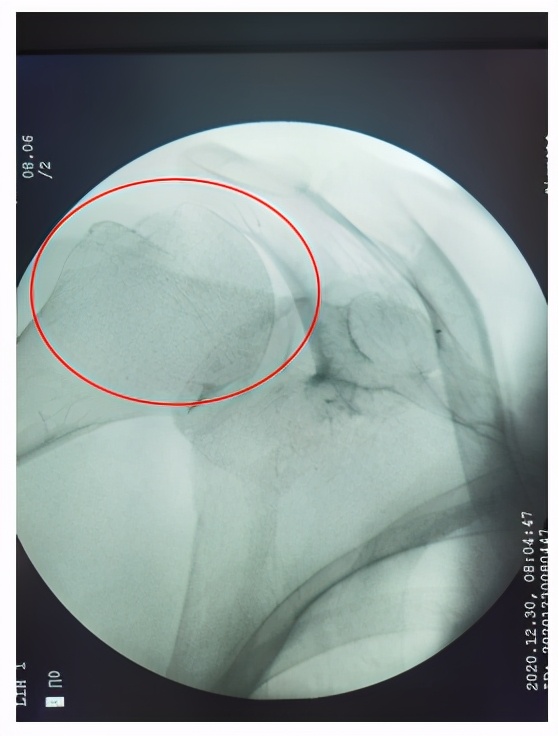

手法复位后X光片

根据这些症状,曹斌医生很快就确定了刘奶奶是右肩关节脱位,在吴向阳副主任医师的指导下,为其进行了手法复位,复位后刘奶奶立即感觉疼痛消失,刘奶奶直呼真是“神奇”。

那么一旦发生肩关节脱位后应该怎么办呢?吴向阳副主任医师指出,发生脱位后应尽快就医进行复位,复位分为手法复位和手术复位,一般前脱位常采取手法复位,但复位前需排除骨折,应尽早、轻柔复位,并采取多种措施减轻患者的疼痛;复位成功后要固定,佩戴前臂吊带3-4周。